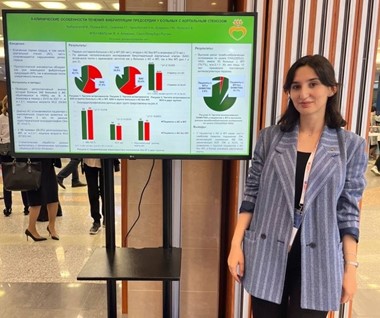

Участие сотрудников лаборатории в конгрессах

Сотрудники НИЛ ежегодно принимают участие в российских и международных кардиологических конгрессах.  В 2019 году Сефиева Г.Г. успешно выступила на Европейском конгрессе кардиологов в Париже с докладом «Изучение и оценка выживаемости беременных женщин с легочной гипертензией в зависимости от тяжести и этиологии данного заболевания». В 2021 году Сефиева Г.Г. выступила на Европейском конгрессе кардиологов с докладом «Тромботические и геморрагические осложнения при беременности, родах и в послеродовом периоде у женщин с протезами клапанов сердца». В 2022 году Сефиева Г.Г. выступила на Российском конгрессе кардиологов с докладом «Тактика антикоагулянтной терапии и тромбогеморрагические осложнения у женщин с механическими клапанами сердца в послеродовом периоде».

В 2019 году Сефиева Г.Г. успешно выступила на Европейском конгрессе кардиологов в Париже с докладом «Изучение и оценка выживаемости беременных женщин с легочной гипертензией в зависимости от тяжести и этиологии данного заболевания». В 2021 году Сефиева Г.Г. выступила на Европейском конгрессе кардиологов с докладом «Тромботические и геморрагические осложнения при беременности, родах и в послеродовом периоде у женщин с протезами клапанов сердца». В 2022 году Сефиева Г.Г. выступила на Российском конгрессе кардиологов с докладом «Тактика антикоагулянтной терапии и тромбогеморрагические осложнения у женщин с механическими клапанами сердца в послеродовом периоде».

Сефиева Г.Г. в своем устном докладе освятила стратегии антикоагулятной терапии у беременных пациенток с протезированными клапанами сердца, а также представила постерный доклад на тему «Особенности гемостаза у пациенток репродуктивного возраста с механическими протезами клапанов сердца».

В рамках XXV Юбилейного Всероссийского научно — образовательного форума «Мать и Дитя-2024», г. Москва Иртюга О.Б. (в соав. с Сефиевой Г.Г., Чыныбековой А.Н.) представила доклад, посвященный особенностям применения антикоагулянтной терапии у беременных пациенток с сердечно-сосудистой патологией.

В ноябре 2024 года Сефиева Г.Г. выступила на VI Общероссийской научно-практической конференции акушеров-гинекологов «Оттовские чтения», г. Санкт-Петербург с устным докладом на тему «Беременность и механический протез клапана сердца: алгоритм антикоагулянтной терапии».